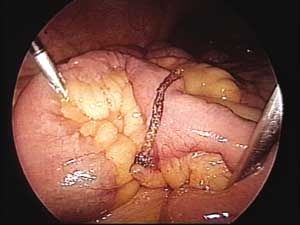

com divertículo de Meckel (Figura 2). Realizamos

a ressecção do mesmo utilizando endogrampeador

linear cortante 45mm (Figura 3).

| Figura 2 _ Divertículo de Meckel: aspecto laparoscópico. | Figura 3 _ Aspecto laparoscópico após a ressecção. |